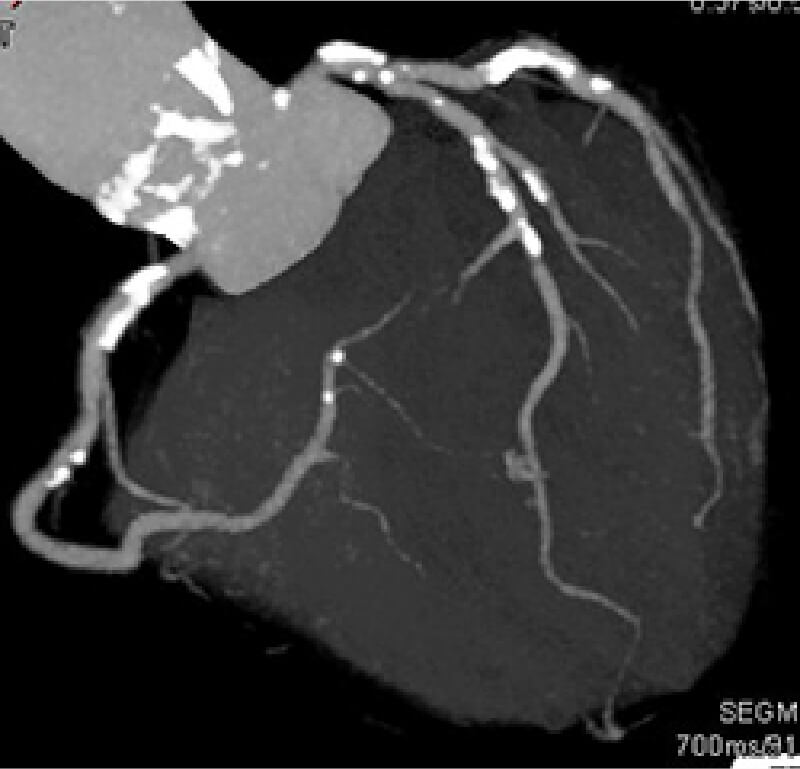

カルシウムスコア測定

心臓に血液を供給するために、心臓を取り囲むようにして存在している血管を冠動脈と呼びます。この冠動脈の石灰化の状態を調べる検査がカルシウムスコア測定です。

動脈硬化が進行して硬くなった部分を石灰化と呼び、レントゲンでは骨のように白く写ります。CT検査で心臓を撮影し、冠動脈の石灰化の量を合計した数値がカルシウムスコアです。カルシウムスコアが高い人ほど冠動脈の動脈硬化が強く、重大な心臓病を起こす可能性が高くなります。そのため、カルシウムスコア測定は虚血性心臓病の早期発見に有効な検査だといえます。生活習慣病のある方・喫煙をされる方・ご家族に同じ病気がある方には、特に受診をおすすめします。

カルシウムスコアはCT検査で測定しますが、造影剤は使用しないため被ばく量も少なく、撮影時間も数秒程度と非常に短い検査 です。カルシウムスコアが100以上の場合、精密検査が必要となります。

画像1)冠動脈のCT画像。(白い部分が石灰化)

画像2)画像1のカルシウムスコア。(1047.90とかなり高い)